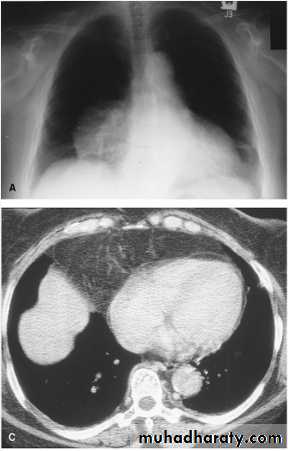

Massive pleural effusion with mediastinal shift to the left.

(A) Chest radiograph

(B) CT coronal reconstruction. A massive effusion displaces the mediastinum to the left. CT shows the important pleural effusion together with the enhanced atelectatic left lung.

Note also the depression of the right hemidiaphragm (arrows).